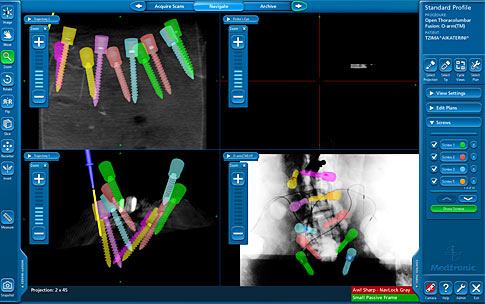

Τα τελευταία χρόνια, ξεκινώντας από τις ΗΠΑ, εξελίχθηκε και εφαρμόστηκε στη χειρουργική της σπονδυλικής στήλης το σύστημα της χειρουργικής πλοήγησης το οποίο επιτρέπει στον χειρουργό να παρακολουθεί την τοποθέτηση των εμφυτευμάτων του σε πραγματικό χρόνο (real time) με την ακρίβεια αξονικού τομογράφου. Το σύστημα αυτό μπορεί να παρέχει στο χειρουργό τη μέγιστη ακρίβεια στον εντοπισμό των ευαίσθητων νευρικών στοιχείων ώστε να τα προστατεύει κατά τη διάρκεια του χειρουργείου. Η ακρίβεια αυτή εκμηδενίζει την πιθανότητα ιατρικού λάθους και την πρόκληση μόνιμων νευρολογικών βλαβών όπως η παράλυση.

Σύμφωνα με τον Δρ. Λυκίσσα, “...η χρήση του συστήματος πλοήγησης κάνει την τοποθέτηση των εμφυτευμάτων στη σπονδυλική στήλη, ιδιαίτερα στην περίπτωση παραμόρφωσης όπως η σκολίωση και η κύφωση, να είναι ασφαλέστερη ακόμη και από αυτή που θα πραγματοποιήσει ο πιο έμπειρος ορθοπαιδικός χειρουργός ή νευροχειρουργός.”